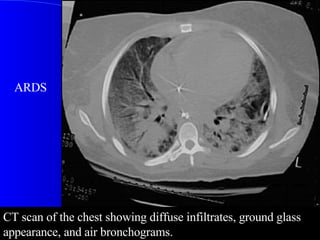

CT scan of the chest showing diffuse infiltrates, ground glass appearance, and air bronchograms.  ARDS

CT scan ofthe chest showing diffuse infiltrates, ground glass appearance, and air bronchograms. ARDS